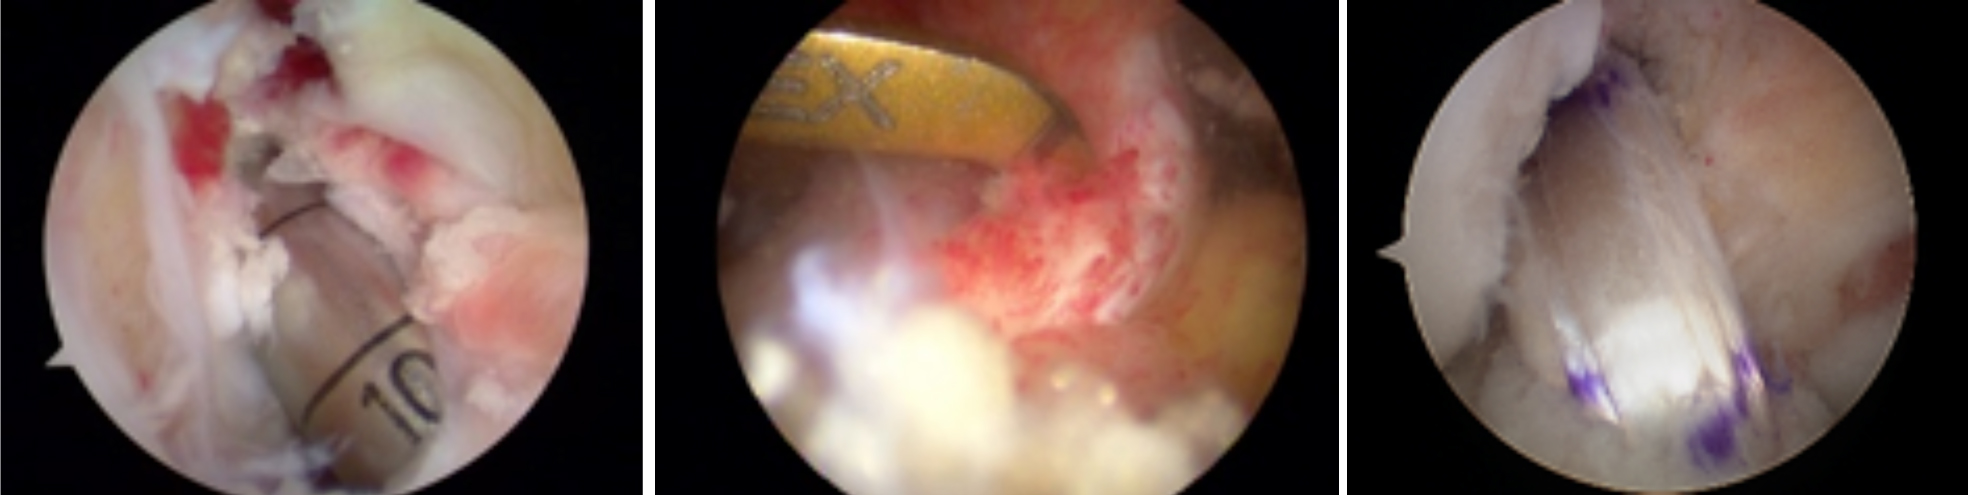

三、微创手术

开展关节镜下交叉韧带单、双股解剖重建技术、膝关节多韧带损伤的一期修复重建术、半月板缝合技术、骨软骨移植技术、同种异体移植治疗交叉韧带损伤、双隧道重建交叉韧带、肩关节镜下肩袖修补和SLAP损伤修补术,及肘、踝、腕、髋关节镜术。专业运动员伤病诊治技术、股骨髋臼撞击综合症、股骨头坏死阶梯治疗技术、骨软骨移植技术

关节镜清理、软骨移植修复

膝关节镜-半月板损伤

膝关节镜-前交叉韧带重建

膝关节镜-关节内游离体